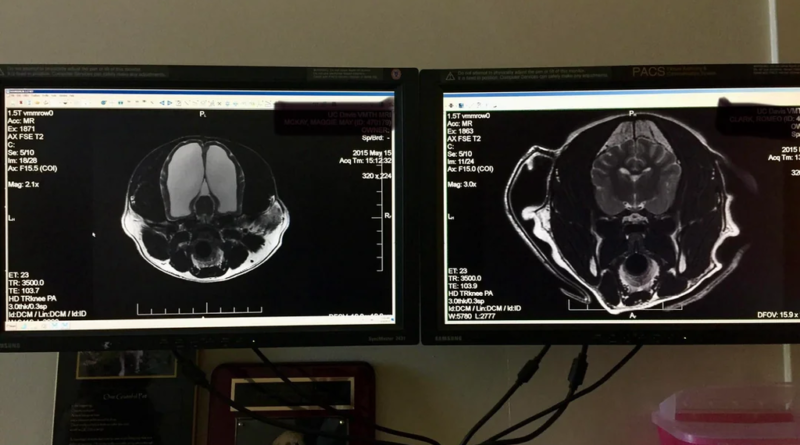

Exames detalhados em um hospital veterinário revelaram que cerca de 95% da cavidade craniana da pastora australiana estava preenchida por líquido, caracterizando uma hidrocefalia severa. Apesar dessa condição alarmante, a cadela mantinha uma vida aparentemente normal, o que surpreendeu seus tutores e veterinários.

A ressonância magnética confirmou a gravidade da situação, mostrando que a maior parte do espaço craniano estava ocupada por líquido, restando apenas uma fração de tecido cerebral funcional. O contraste entre a imagem do cérebro da cadela e a de um cão saudável foi impressionante.